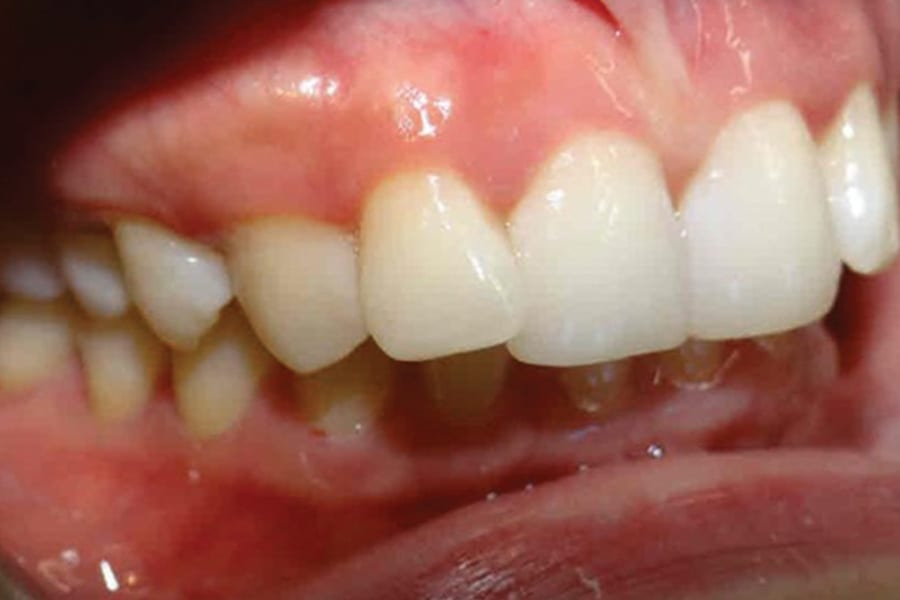

A 35-year-old woman presented with concerns of crowding, bruxism, and bite misalignment, which were associated with a class II malocclusion that would require a combination treatment of expansion, distalization, and molar derotation. ClearCorrect® aligner therapy (Straumann, clearcorrect.com) was selected as the primary modality, as the patient requested a non-invasive, esthetic treatment. The treatment plan was designed to be completed within 6 months of active aligner therapy. Class II elastics were prescribed, and the ClearCorrect FLEX case plan was chosen to allow for refinements, as needed. After comprehensive digital records were taken, the first set of aligners was delivered, engagers were bonded, and the patient was instructed to wear aligners on a 14-day cycle with full-time class II elastic wear. To enhance efficiency, more engagers were placed, including posterior attachments, to maximize control over molar distalization and anchorage. Interproximal reduction of 0.3 mm was performed in a few contacts at the initial appointment to facilitate space closure and alignment. Due to the complexity of the correction and the patient’s history of bruxism, a lower 3-3 bonded retainer was placed, and retainers were fabricated for both arches. The patient expressed a high level of satisfaction with the ClearCorrect aligner therapy, noting the comfort and esthetics of the aligners and the ability to achieve a fully corrected class II occlusion in just 6 months of treatment.